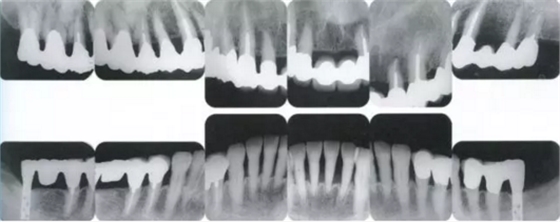

▲圖19-12

同時期的X光片。

佩戴最終修復體時的X光片。骨邊緣水平平坦,探診值維持在1~2mm。